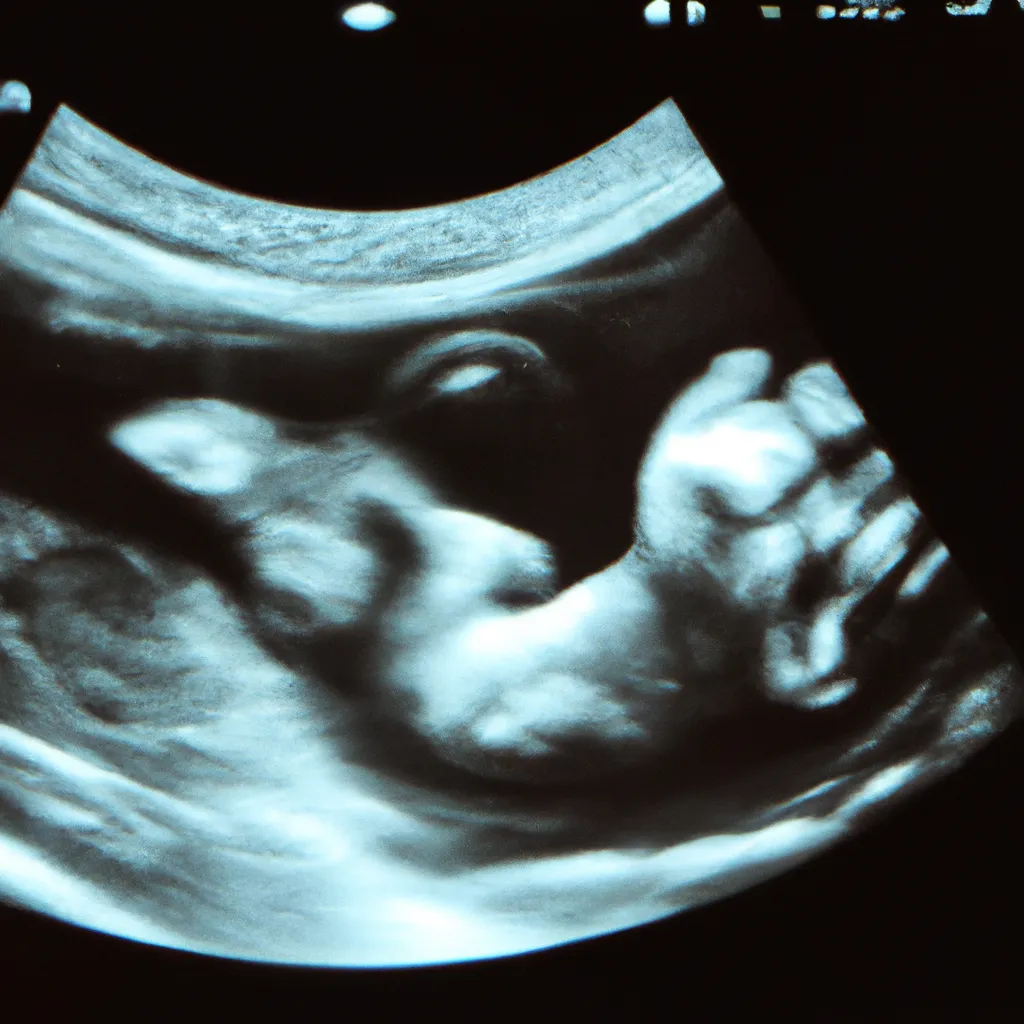

Warto również wspomnieć o metodzie liczenia ciąży za pomocą ultrasonografii. Badanie USG wykonywane w pierwszym trymestrze może pomóc w dokładniejszym określeniu wieku ciążowego. Lekarz mierzy długość ciemieniowo-siedzeniową płodu (CRL), co pozwala na precyzyjne określenie wieku ciąży. W przypadku różnicy między datą obliczoną na podstawie LMP a datą z USG, lekarz może zdecydować się na korektę terminu porodu.